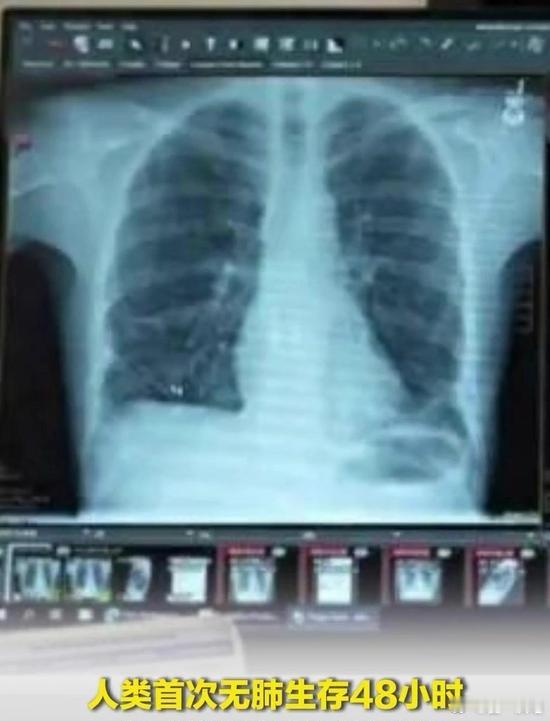

人类首次无肺生存48小时!人类首次无肺生存48小时 美国西北大学医学院团队通过革新版人工肺系统,首次实现人类无肺生存48小时并成功完成双肺移植。一名33岁患者因流感导致双肺坏死,切除后依靠该系统维持心脏血流及氧合,术后近三年心肺功能正常。